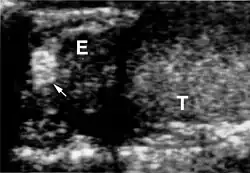

Nerki

W nerkach pacjentów z zespołem von Hippla-Lindaua rozwijają się zmiany nienowotworowe o charakterze torbieli prawdziwych (cystes renis), zmiany nowotworowe łagodne o charakterze torbielakogruczolaków (cystadenomata) i nowotwory złośliwe – rak nerkowokomórkowy (carcinoma renocellulare). Torbiele nerek są bezobjawowe. Rak nerki rozwija się w obrębie torbieli, zazwyczaj jest to rak jasnokomórkowy (clear-cell carcinoma). W zespole von Hippla-Lindaua dotyczy ponad 70% pacjentów[1] – jest to najczęstsza przyczyna rodzinnego występowania nowotworu złośliwego nerki. Rozwija się w młodym wieku, często obustronnie i wieloogniskowo; późno daje przerzuty.